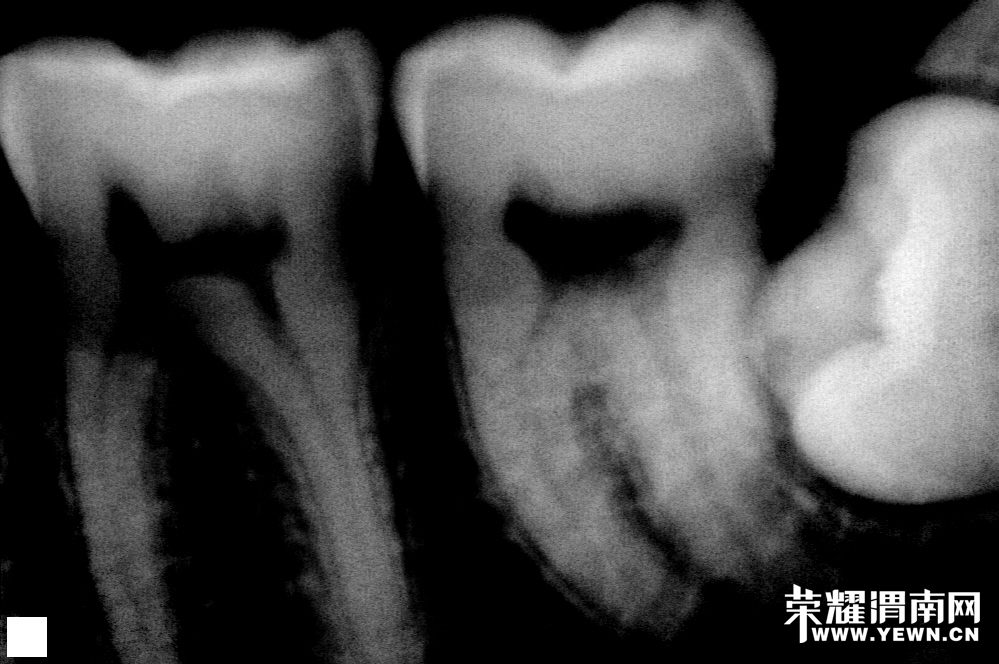

看看这是什么

医生给我拔了两个小时,血都流干了快

你那个长的太深了,肯定特别疼,哎……智齿太害人了

哈哈,我的和你的一样啊,我两边都有啊!拔牙(智齿)太难受了!而且我那还很难啊,是横着的!

我也是横着长的,而且也是两个,同病相怜呀

还有一个呢!医生说下次再拔另外一个